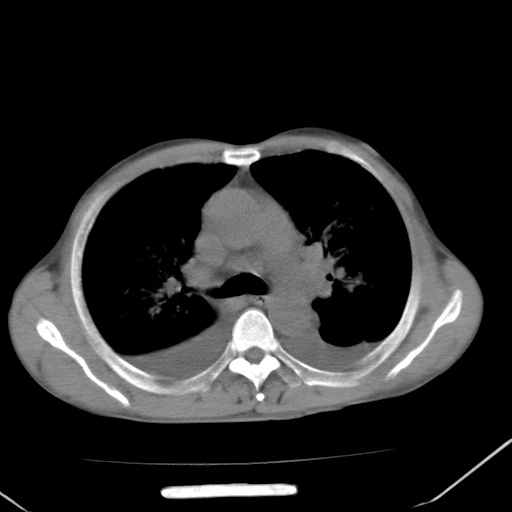

男、42岁、咯血3天。既往有甲亢、贫血、血尿蛋白尿史多年。血象:wbc:6.   中性粒:70.6%。

双肺野对称性磨玻璃影,分布于内中带,双侧胸水,患者有咯血。

双肺野广泛对称性磨玻璃影、实变影,以肺门为中心,主要分布于内中带,符合典型肺泡性肺水肿;伴双侧胸腔少量游离积液。结合患者既往病史且咯血就诊,支持多因素(尿毒症等)所致之肺水肿、肺出血、胸水;影像表现暂不考虑心源性水肿,且症状也不太符。需密切随诊结合临床治疗等进一步明确。

心影增大密度略低,双肺磨玻璃样高密度影及双侧胸腔积液,考虑心功能不全继发双肺肺水肿及双侧胸腔积液。心影密度略低,考虑贫血所致。